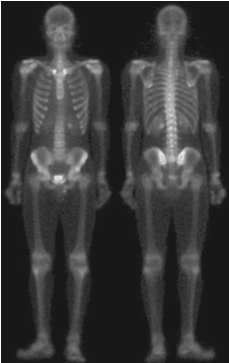

실제로 일반적인 샤프닝 영상에 비해서 훨씬 깔끔한 영상을 얻은 것을 볼 수 있습니다. 하지만 여전히 밝기값이 낮기 때문에 마지막으로 거듭제곱-법칙 변환을 적용해여 아래의 최종 영상을 얻을 수 있습니다.

위의 과정이 의미하는 바는 단일 기법으로는 가능하지 않은 결과를 얻기 위해서 결합될 수 있는 프로세스들이 있음을 의미합니다. 이때 어떤 프로세스들을 결합할 지는 어떤 문제를 해결하느냐에 달라지게 됩니다.